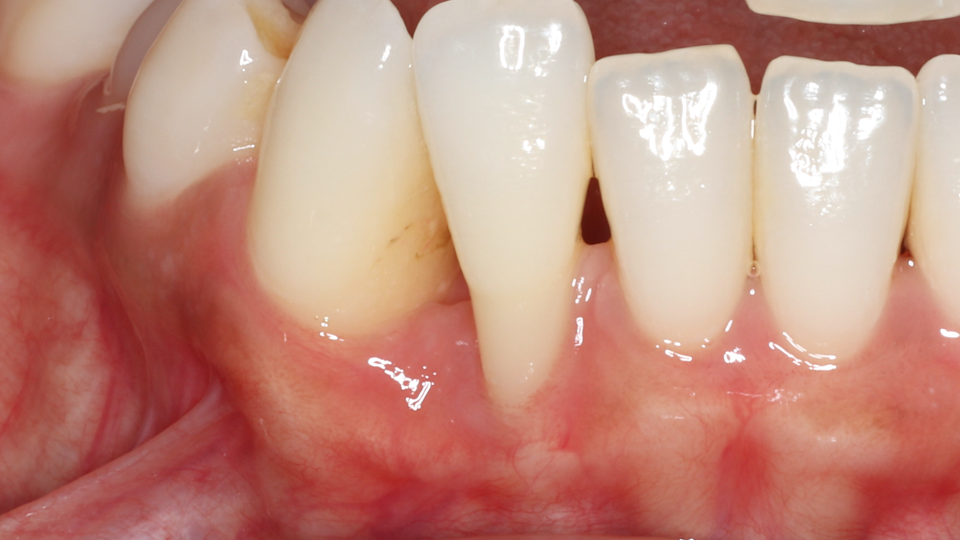

This patient has healthy thick gum tissue. The free gingiva is the cuff surrounding the tooth and the attached gingiva is the thick tissue attached to the bone. Both of these are made of keratinized tissue.

Take a closer look at the difference between the two areas in this patient's mouth. The teeth surrounded by thick, firmly attached protective tissue show no plaque buildup, no inflammation, and stable, healthy gum levels. In contrast, the sites that lack this protective tissue are visibly inflamed and collecting bacteria along the gumline, which is driving progressive recession. Without intervention to rebuild that protective barrier through grafting, the affected teeth would continue to lose gum tissue and bone support over time, ultimately putting them at risk of being lost entirely.